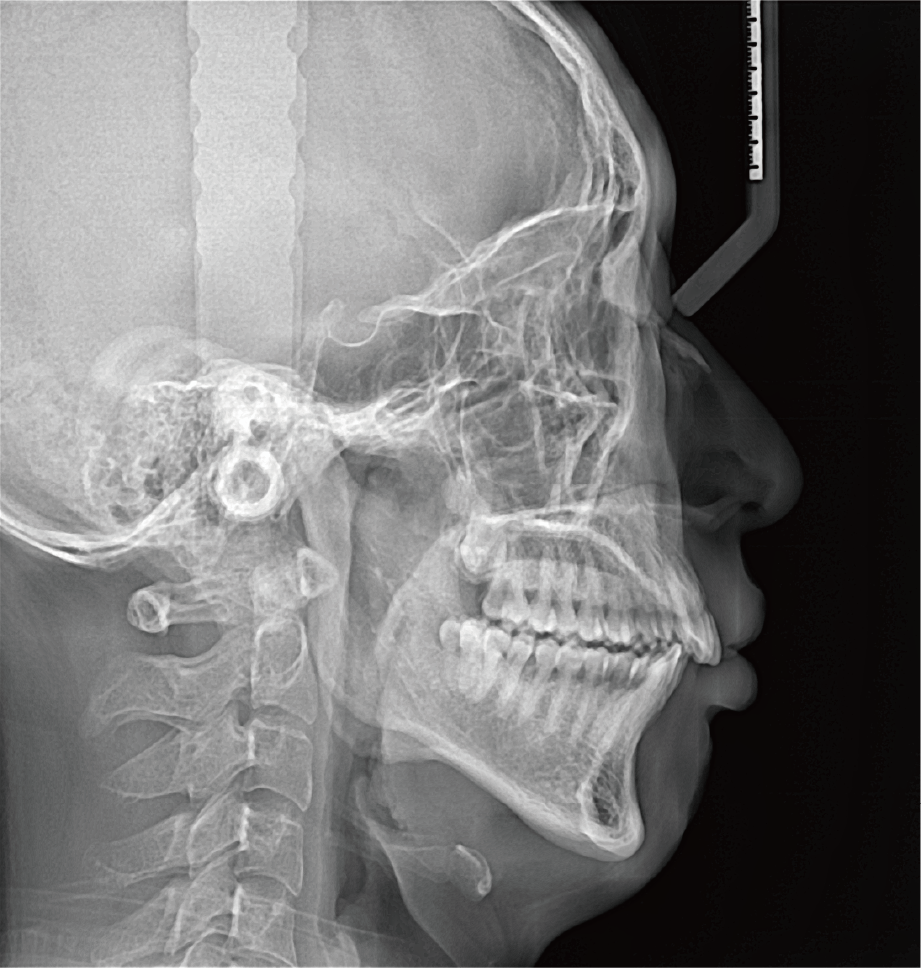

临床样片